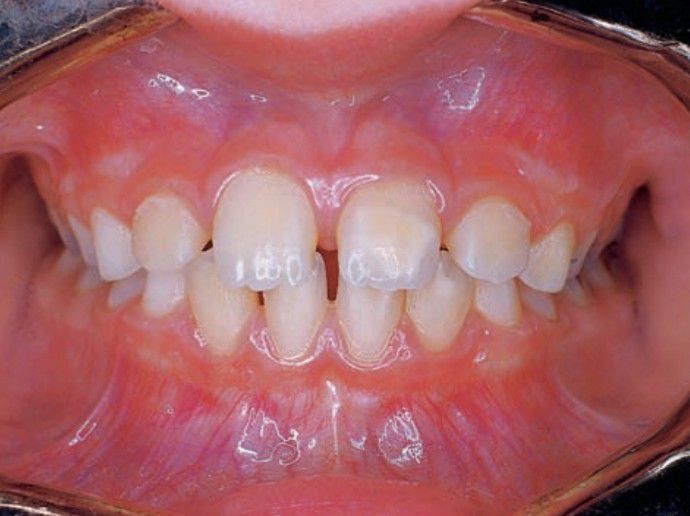

Turner's tooth

Qualitatively defective enamel, in which normal amounts of enamel are produced but are hypomineralized, is known as enamel hypocalcification or Turners tooth